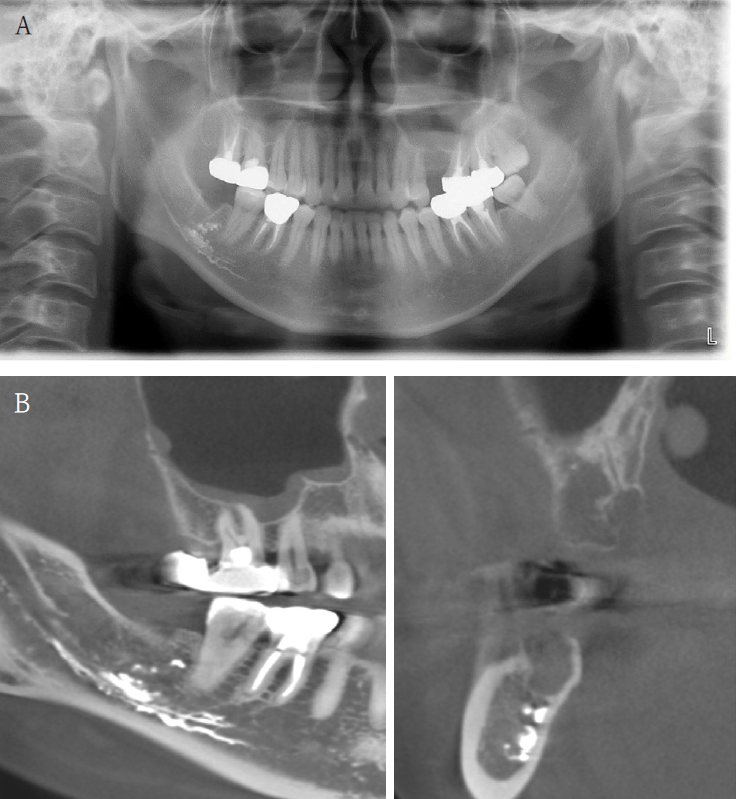

Case 4

An 18-year-old male developed numbness in the right lower lip, gingiva, and chin following endodontic treatment of the mandibular right first molar (#46) at a military hospital 2 weeks ago. A panoramic radiograph and multi-detector computed tomography (MDCT) revealed extruded Calcipex II in proximity to the IAN (Fig. 6). Neurologic testing confirmed severe hypoesthesia in the right mentum region. Thermal discrimination was absent across a broad area of the right lower lip and chin. The patient’s subjective discomfort was rated as VAS 2. The patient underwent foreign body removal, nerve transposition, and bone grafting under general anesthesia (Fig. 7). At one-week postoperative follow-up, neurosensory testing showed little to no improvement. At the five-month follow-up, repeated neurosensory testing demonstrated meaningful improvement in directional discrimination and pin-pressure nociceptive discrimination, despite the continued presence of hypoesthesia. At the 17-month follow-up, testing revealed further improvement, including recovery of static light touch sensation, with overall symptoms classified as mild hypoesthesia. However, the patient reported worsening subjective discomfort, with a VAS 5, reflecting a discordance between objective sensory recovery and subjective symptom persistence.